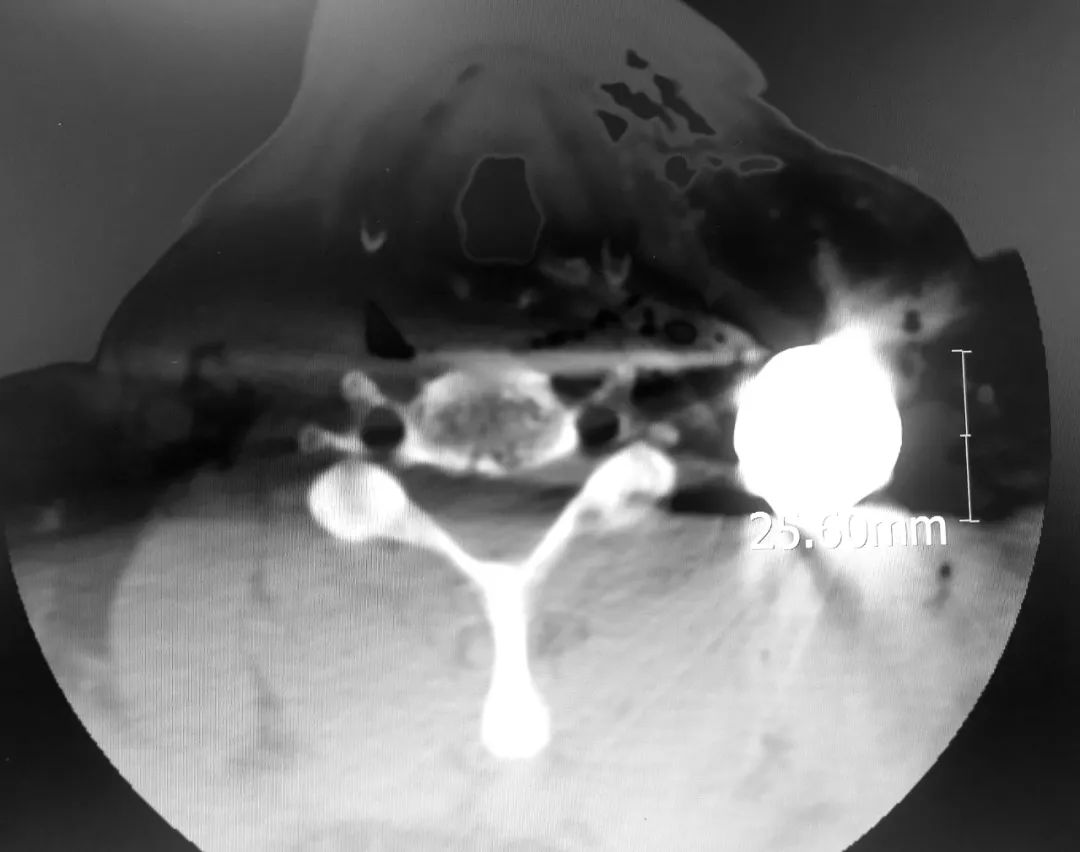

患者术前CT片

患者术前三维CT

患者为老年男性,被金属异物从胸壁射入造成一处大小约6cm×8cm的伤口,金属异物残留在颈部,导致患者锁骨开放性骨折、肋骨多发骨折,并出现肺挫伤,出血量大,送至我院时已出现失血性休克,病情危重。

急诊科创伤小组,创伤骨科和手足显微外科,手术室医护团队立即启动急诊手术流程,从术前准备到顺利完成手术,用时仅仅40分钟,成功取出患者颈部异物(共取出2个圆形中空金属异物,大小约3-4cm×5-6cm),术中未损伤颈部血管、神经,术后患者生命体征逐渐稳定,转入创伤骨科和手足显微外科病房进一步救治。